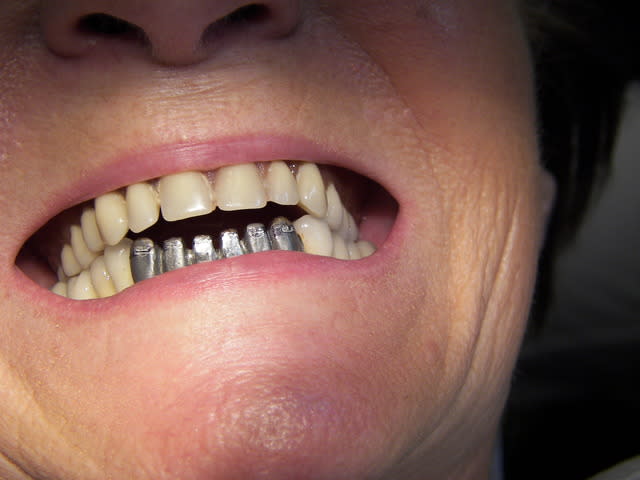

Voilà tout de même une dent que la majorité des intervenants ont jugé à extraire.

Avouez que c'est étonnant...

J'en connais pas mal qui feraient un (ou deux, ça cote plus) amalgames...

La question est donc vaut il mieux extraction/implant ou un amalgame... ou alors la réponse est entre les deux :))